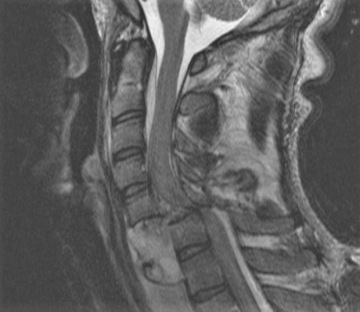

Pro vaši informovanost bych ještě rád zmínil mechanismus vzniku úrazu. Pokud je skákaná tzv. šipka, je prvním tvrdším letícím předmětem o vysoké kinetické energii hlava. Poté následuje krční páteř a dále opět část těla s vyšší tuhostí, tedy hrudní koš, následovaný břichem a dolními končetinami. Veškerá decelerační energie vznikající nárazem hlavy na překážku (dno) se tedy koncentruje na místo nejmenšího odporu, tedy krční páteř (samozřejmě nelze vyloučit, že je při skoku poraněna i hlava nebo hrudní páteř). Dochází k rozlomení obratle (nejčastěji C5, nebo C6 a C7) s tlakem úlomku do páteřního kanálu a poškození míchy.